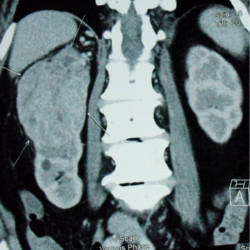

The purpose of testing is to diagnose and stage the Tumour :

Stage I – a tumour less than 7cm in the kidney.

Stage II – a tumour larger than 7cm in the kidney.

Stage III – a tumour in the kidney and nearby lymph nodes, main blood

vessels and tissues.

Stage IV – cancer may spread to other organs through blood vessels

and lymph nodes.